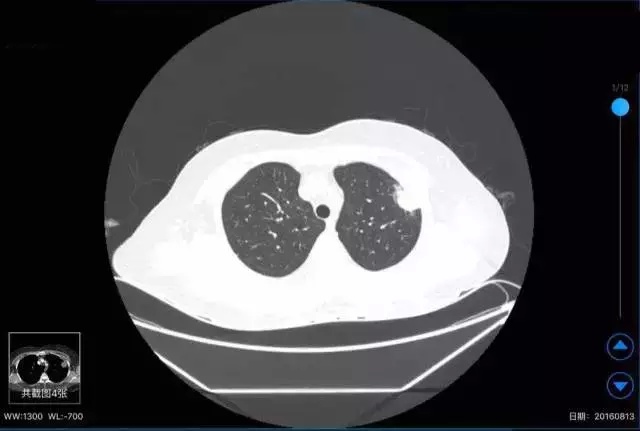

患者咳血胸痛一周。

肺部占位。

病变考虑为肿瘤或炎症,血象不高,肿瘤序列正常,结核试验阴性,ect阴性。请问贺主任意见?

左肺上叶尖段可见4.5*1.8cm的楔形实变病灶,尖端朝向肺门,周边可见浸润样实变。病灶中央可见低密度的无强化区,可见引流支气管;相邻胸膜可见增厚。会诊意见: 左肺上叶实变病灶,中央有液化坏死,考虑炎症性病变,霉菌、隐球菌或结核,请结合临床和治疗变化。供参考。建议最后提供原始轴位图像。